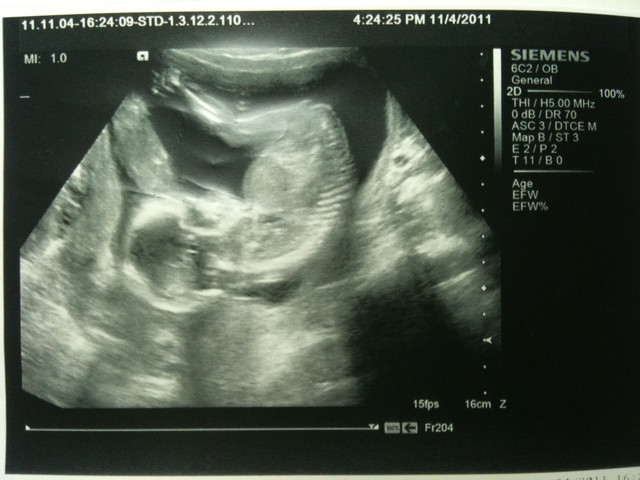

第16 weeks 的產檢 老大用賽車手的精神火速的從公司趕到醫院

非常幸運的 我們能一起感受小朋友在我的肚子裡的成長

而且孫醫生還很貼心的要我稍微躺下來一點 才能看到螢幕

這次的一般性檢查都正常 小朋友的週數還比原本的週數大一週

這次的檢查小插曲是

孫醫生一邊檢查曆行檢查 突然問了我們 上次是否有告知我們性別

我和老大一起說 沒有

接下來 孫醫生就用迅雷不及掩耳的速度告知我們

孫醫生 : 是男生

呵

其實 這次的產檢我們的確是想要來看性別的

但網路上很多媽媽都分享說 假如小朋友腳沒有打開

可能不能看的到性別

所以 我本來想說要是醫生沒有看到

我再向醫生提問

結果 讓我和老大的反應都是 呆掉

反而嚇到孫醫生本人 (箭頭所指處)

2011/11/4

第三次去產檢 確認上次抽血檢查結果

抽血結果:正常 有德國麻疹抗體

驗尿結果:膀胱有點發炎 開消炎藥改善

本次自費檢查第二孕期母血唐氏症篩檢 900 元

醫生公布小朋友性別: BOY

小朋友的身體狀況: 一切正常 大小約為17週大小(實際16週)

小朋友身高(頭到屁股):10 cm

箭頭所指處為小朋友的性別